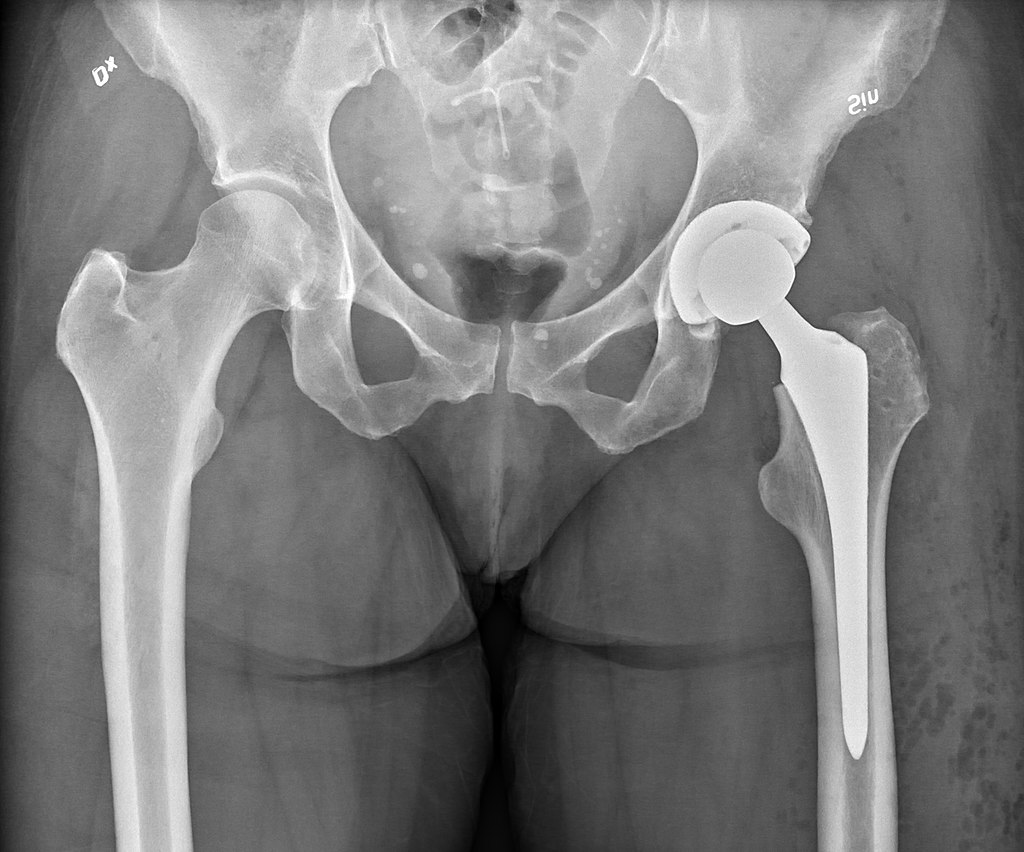

Эндопротезкунонии буғуми рону кос